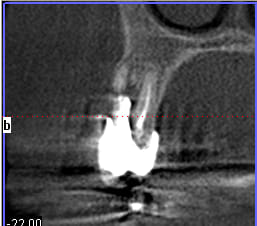

un petit exemple de ce matin: extraction des piliers 12 et 14, curetage, comblement avec du bio-oss de la dépression osseuse vestibulaire au niveau de l'inter 13, comblement des alvéoles 12 et 14 au genos et recouvrement par 2 pédicules conjonctifs. Temporisation avec un partiel amovible.

Niveau 12 slt3od - Eugenol

Niveau inter trai6z - Eugenol